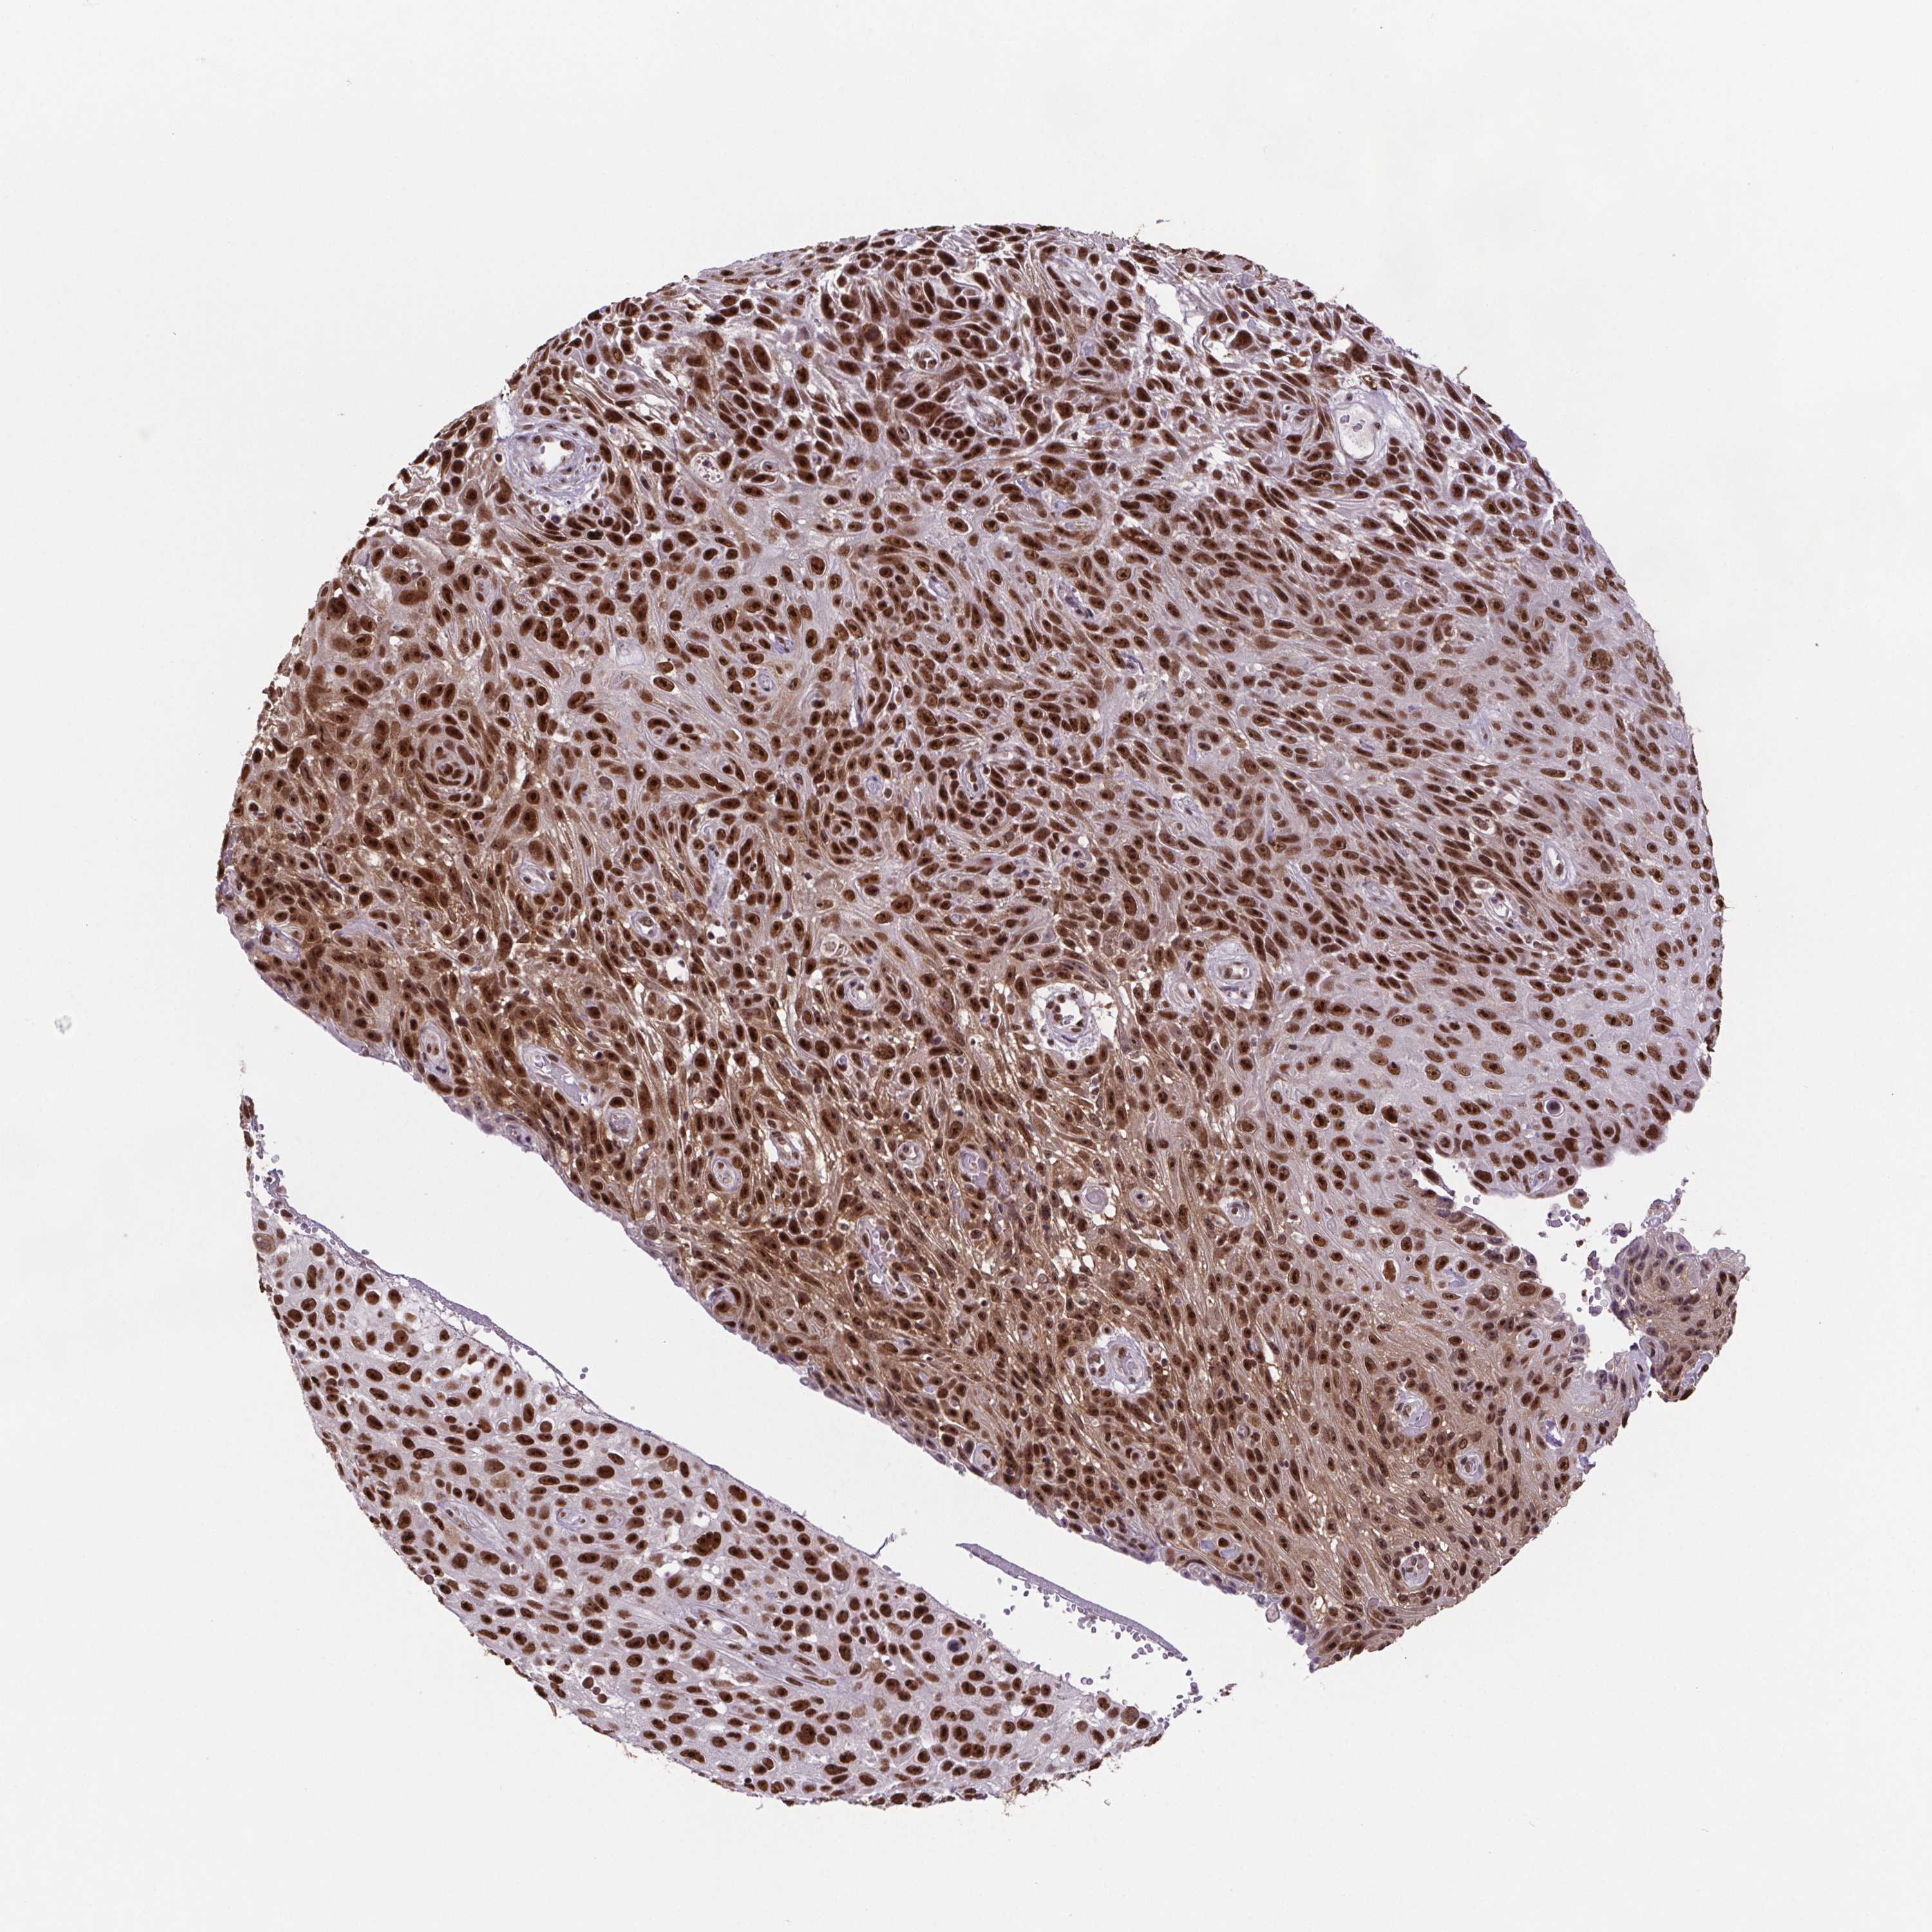

SKIN CANCER - Protein expressioni

A mouse-over function shows sample information and annotation data. Click on an image to view it in a full screen mode. Samples can be filtered based on level of antibody staining by selecting one or several of the following categories: high, medium, low and not detected. The assay and annotation is described here.

Antibody stainingi

Antibody staining in the annotated cell types in the current human tissue is reported as not detected, low, medium, or high, based on conventional immunohistochemistry profiling in selected tissues. This score is based on the combination of the staining intensity and fraction of stained cells.

Each image is clickable and will lead to virtual microscopy that enables deeper exploration of all samples and also displays staining intensity scores, fraction scores and subcellular localization as well as patient and tissue information for each sample.

Antibody HPA064930

Staining

High

Medium

Low

Not detected

Intensity

Strong

Moderate

Weak

Negative

Quantity

>75%

75%-25%

<25%

None

Location

Nuclear

Cytoplasmic/membranous

Cytoplasmic/membranous,nuclear

Basal cell carcinoma

Squamous cell carcinoma, NOS